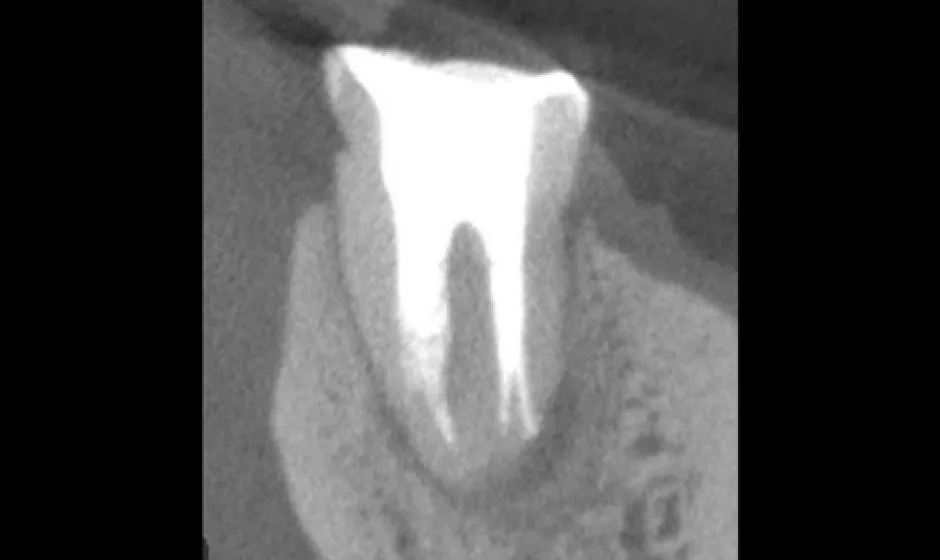

可能な限り歯を残す精密治療

できるだけ歯を守るために、削る量を抑え、神経を残せる可能性も視野に入れながら治療方針を検討します。

歯科用CTで状態を立体的に把握し、必要に応じてマイクロスコープを用いて細部まで確認しながら処置を実施。見えにくい部分ほど丁寧に対応することで、治療精度を高め、再治療のリスクをできる限り減らすことにもつなげます。 -

01精密根管治療

「抜くしかない」と言われた歯でも、根の中の感染を適切に抑えられる治療技術があれば、歯を残せる可能性があります。根管は非常に細く複雑で、わずかな取り残しが痛みや腫れの再発につながることもあるため、当院では必要に応じてCTやマイクロスコープを活用し、原因を見極めながら丁寧に処置を進めます。

大杉歯科医院が大切にしているのは、早く終える治療ではなく、歯を守る治療。津市で、できるだけ天然歯を残したい方の選択肢になれるよう取り組んでいます。症例1

症例2

- 治療名

- マイクロスコープとラバーダムを使用した精密根管治療

- 患者様

- 40代女性

- 執刀医

- Dr. 大杉

- 治療期間

- 3ヶ月

- 治療費

- 精密根管治療:130,000円(税込)

築造:40,000円(税込)

セラミック:130,000円(税込) - リスク

- 治療中〜治療後に痛みが出る場合あり

再感染・治癒不全の可能性

補綴後も定期管理が必要